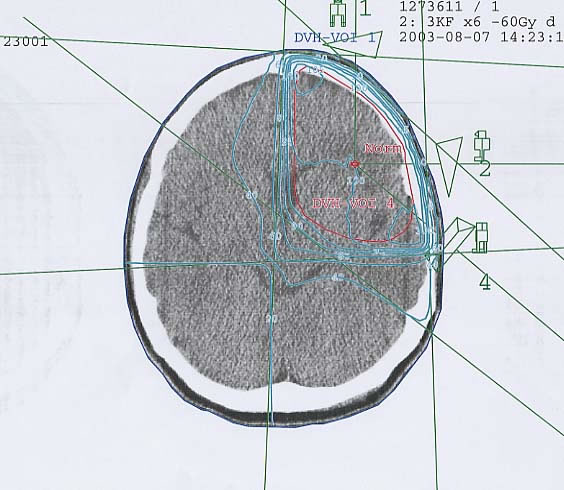

Hirntumore: Bestrahlungsplan

Einführung aktuelle Bilder - Einführung Bestrahlungspläne - Einführung Demonstration